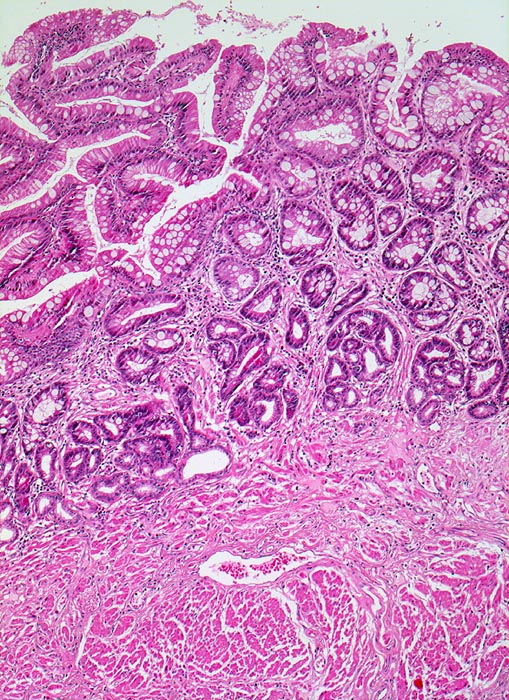

• Distales Ösophagusteilstück.

• Von oben nach unten: Magenschleimhaut vom Fundustyp mit spezialisierten Magendrüsen, Ösophagusschleimhaut (nicht verhornendes Plattenepithel), Schleimhaut vom Kardiatyp (villoglanduläre Oberfläche, Zylinderzellen) mit herdförmig intestinaler Metaplasie (Becherzellen und Paneth'sche Körnerzellen mit rotem granulärem Zytoplasma) vereinbar mit Barrettmukosa.

• Mässiggradige chronische (Plasmazellen), geringgradig aktive (neutrophile Granulozyten) Entzündung der Magenschleimhaut.

• Keine Epitheldysplasie (intraepitheliale Neoplasie) im Bereich der Barrettmetaplasie.